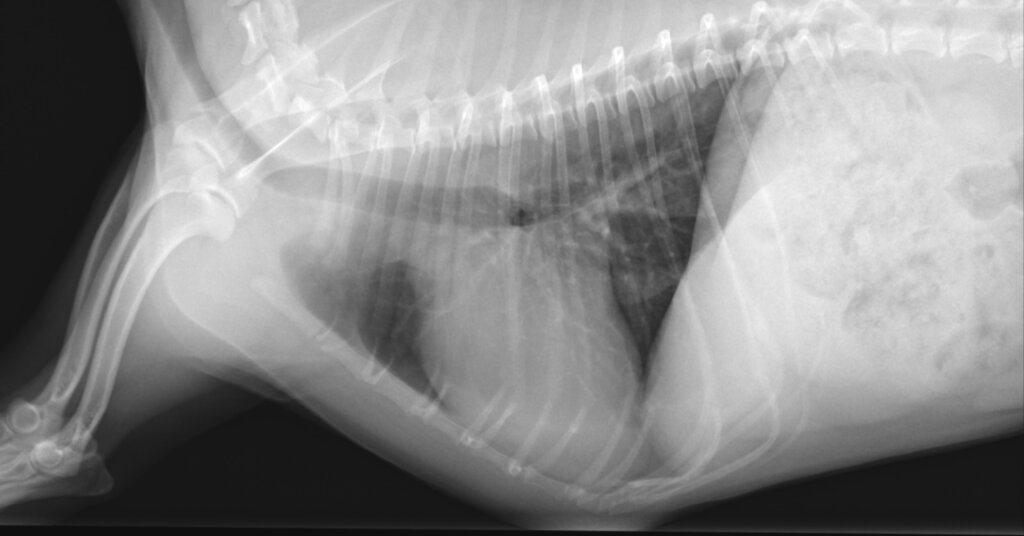

手術後

■ 術後経過

術後経過は良好で、大きな合併症は認められませんでした。

術後1か月:

• 僧帽弁逆流は消失

• LA/Ao:1.43

• LVIDDN:1.62

術後3か月:

• LA/Ao:1.29

• LVIDDN:1.40

心拡大は明らかに改善し、内服薬はすべて中止となりました。

術後6か月現在も、臨床徴候なく安定しています。